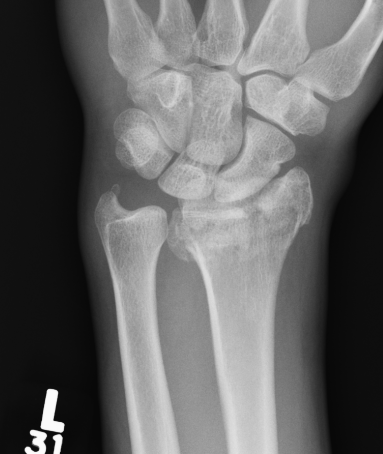

Distal Radius Angles

- radial volar tilt 11°

- radial inclination 22°

- radius is 11 mm longer than ulna

- ulna variance 2mm positive on average